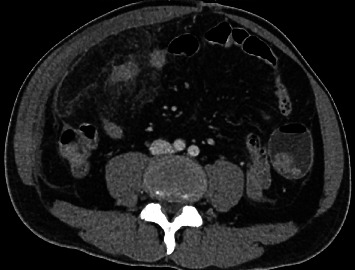

Omental infarction was first described in 1896 mimics other causes of acute abdomen. Improved imaging modalities such as ultrasound and CT scans, have enhanced preoperative diagnosis with conservative management emerging as a treatment option. We report the case of a 51-year-old man presenting with epigastric pain migrating to the right iliac fossa, fever, nausea and anorexia. Examination revealed a stable patient with a right lumbar mass (5 cm × 6 cm) and rebound tenderness. CT imaging identified fat stranding near the ascending colon and hepatic flexure (6 cm ×10 cm ×10 cm) with peritoneal thickening. He underwent exploratory laparotomy, omentectomy and peritoneal washout, which revealed an infarcted omentum (8 cm × 8 cm) and 200 ml of haemoserous fluid. The patient recovered well postoperatively. A systematic search of the literature identified 237 articles reporting 479 cases of omental infarction, with clinical data extracted for analysis. Male predominance was observed (2:1) and 326 patients (68.1%) underwent surgical intervention. Conservative management was successful in 121 patients (25.3%), while 32 (6.7%) required surgery following failed conservative treatment. Among those managed surgically, the most common preoperative diagnosis was appendicitis. CT imaging was performed in 245 cases (51.1%), of which 103 (42.0%) within this group were successfully managed conservatively, while 26 (10.6%) required surgical intervention after conservative failure. Omental torsion was diagnosed preoperatively in 220 patients (45.9%); in this subset, 21 (9.5%) underwent surgery after failed conservative management and only 5 (2.3%) were successfully treated conservatively. While omental infarction can often be managed conservatively, surgery remains a key treatment for intractable pain or omental torsion, where conservative management failure rates are high.